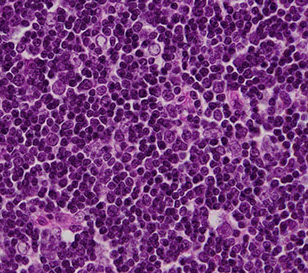

Histologically subclassified as A, AB, or B1-B3, based on "organotypical" features (i.e. histologic resemblance to normal thymic development)

- B1-B3 more epithelioid

-- B1 has more lymphs and less epithelioid cells, B3 has less lymph and more epithelioid cells

- B2 intermediate, with some epithelial cell clusters

IHC: thymocytes (immature lymphs) + for CD99, CD1a and TdT; epithelial cells CK / p63+

- negative CD5 and CD117 (vs thymic carcinoma)

DDx: T-LBL, thymic hyperplasia, thymic carcinoma